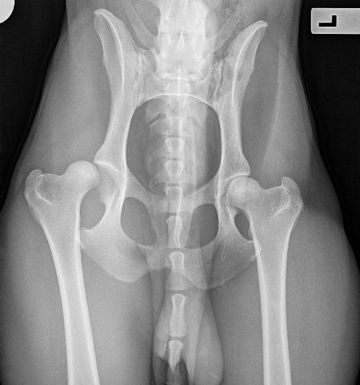

Back to Surgery Information Pet Owner Information Hip Luxation What is Hip Luxation? Hip luxation occurs when the femoral head or “ball” of the “ball-and-socket” joint comes out of the acetabulum or “socket”. In most cases, hip luxation is caused by major trauma, such...